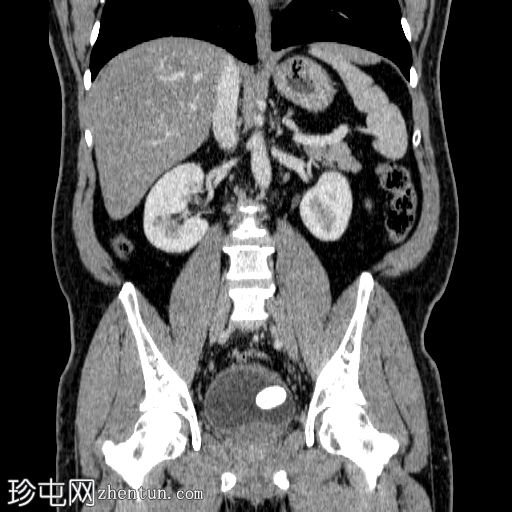

膀胱结石

左侧阴囊和阴茎疼痛,排尿时尿流细弱。

年龄:45岁

性别:男

冠状位

平扫

在左侧输尿管膀胱连接处可见一枚24×15 mm的大膀胱结石。膀胱壁轻度弥漫性增厚,厚度约6 mm,提示膀胱炎。

左肾上极发现一单纯性皮质囊肿,Bosniak I 型,大小为 13 mm。

可见多个副脾(脾小体),位于主脾实质的上方和下方,在影像学各期均表现出与脾脏相似的衰减值。

肝脏弥漫性脂肪浸润。

膀胱结石可引起持续性泌尿系统症状,例如不适、排尿困难和尿频。在某些情况下,结石可能移动到尿道口并阻塞尿液排出。此外,膀胱结石还可能因膀胱刺激和排尿不尽而导致反复泌尿道感染。